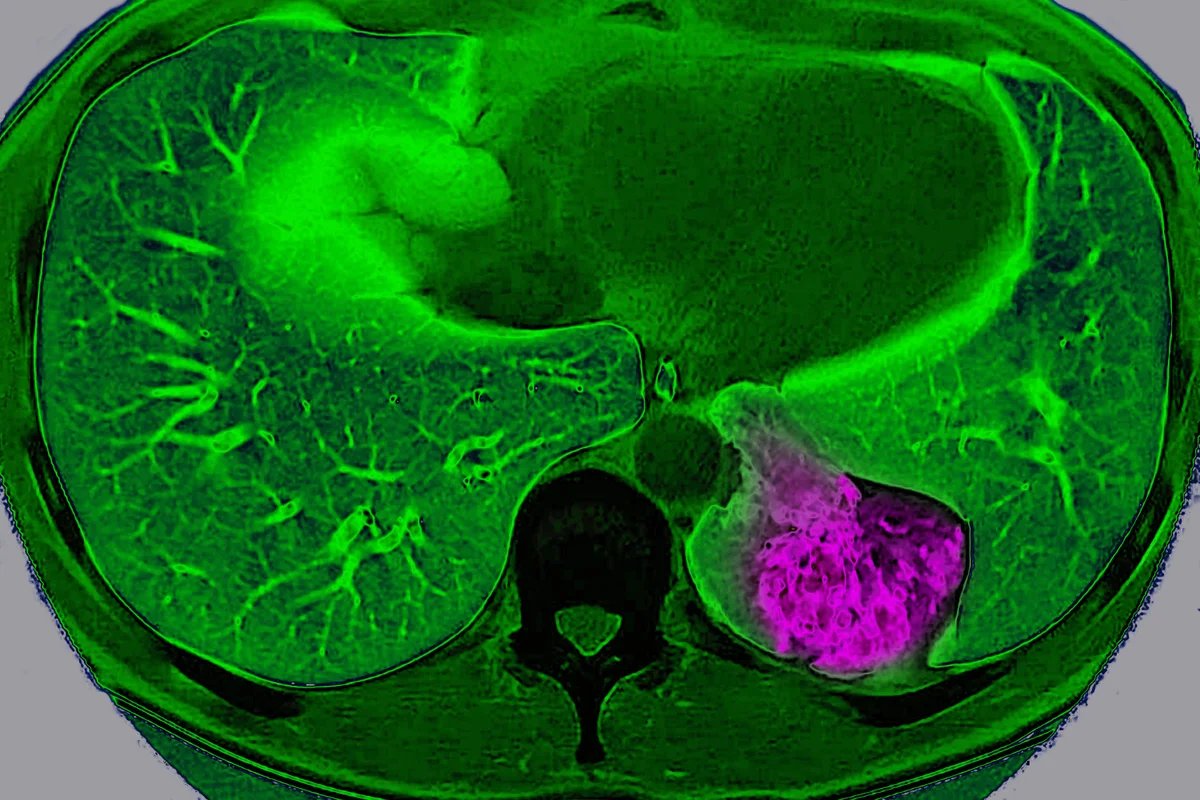

MRI scan of the chest showing lung cancer

Lung cancer on the left pulmonary lobe, seen on a radial section MRI scan of the chest.

BSIP/Universal Images Group via Getty Images